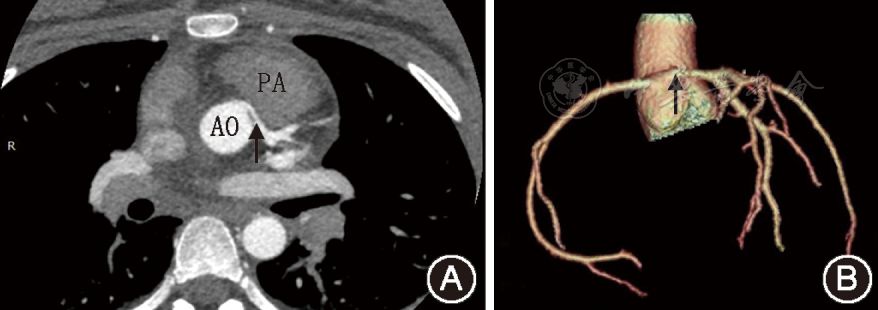

心血管疾病研究儿童左冠状动脉异常起源于右冠状窦伴动脉间行程四例

图片尺寸878x310